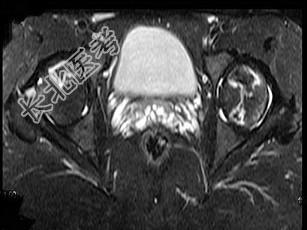

- 单项选择题男,24岁, 曾有外伤史,两侧髋部疼痛不适数月, 结合所提供的图像,最可能的诊断是 ( )

A、股骨头无菌性坏死

B、髋关节退行性变

C、未见异常

D、化脓性骨关节炎

E、类风湿关节炎两侧